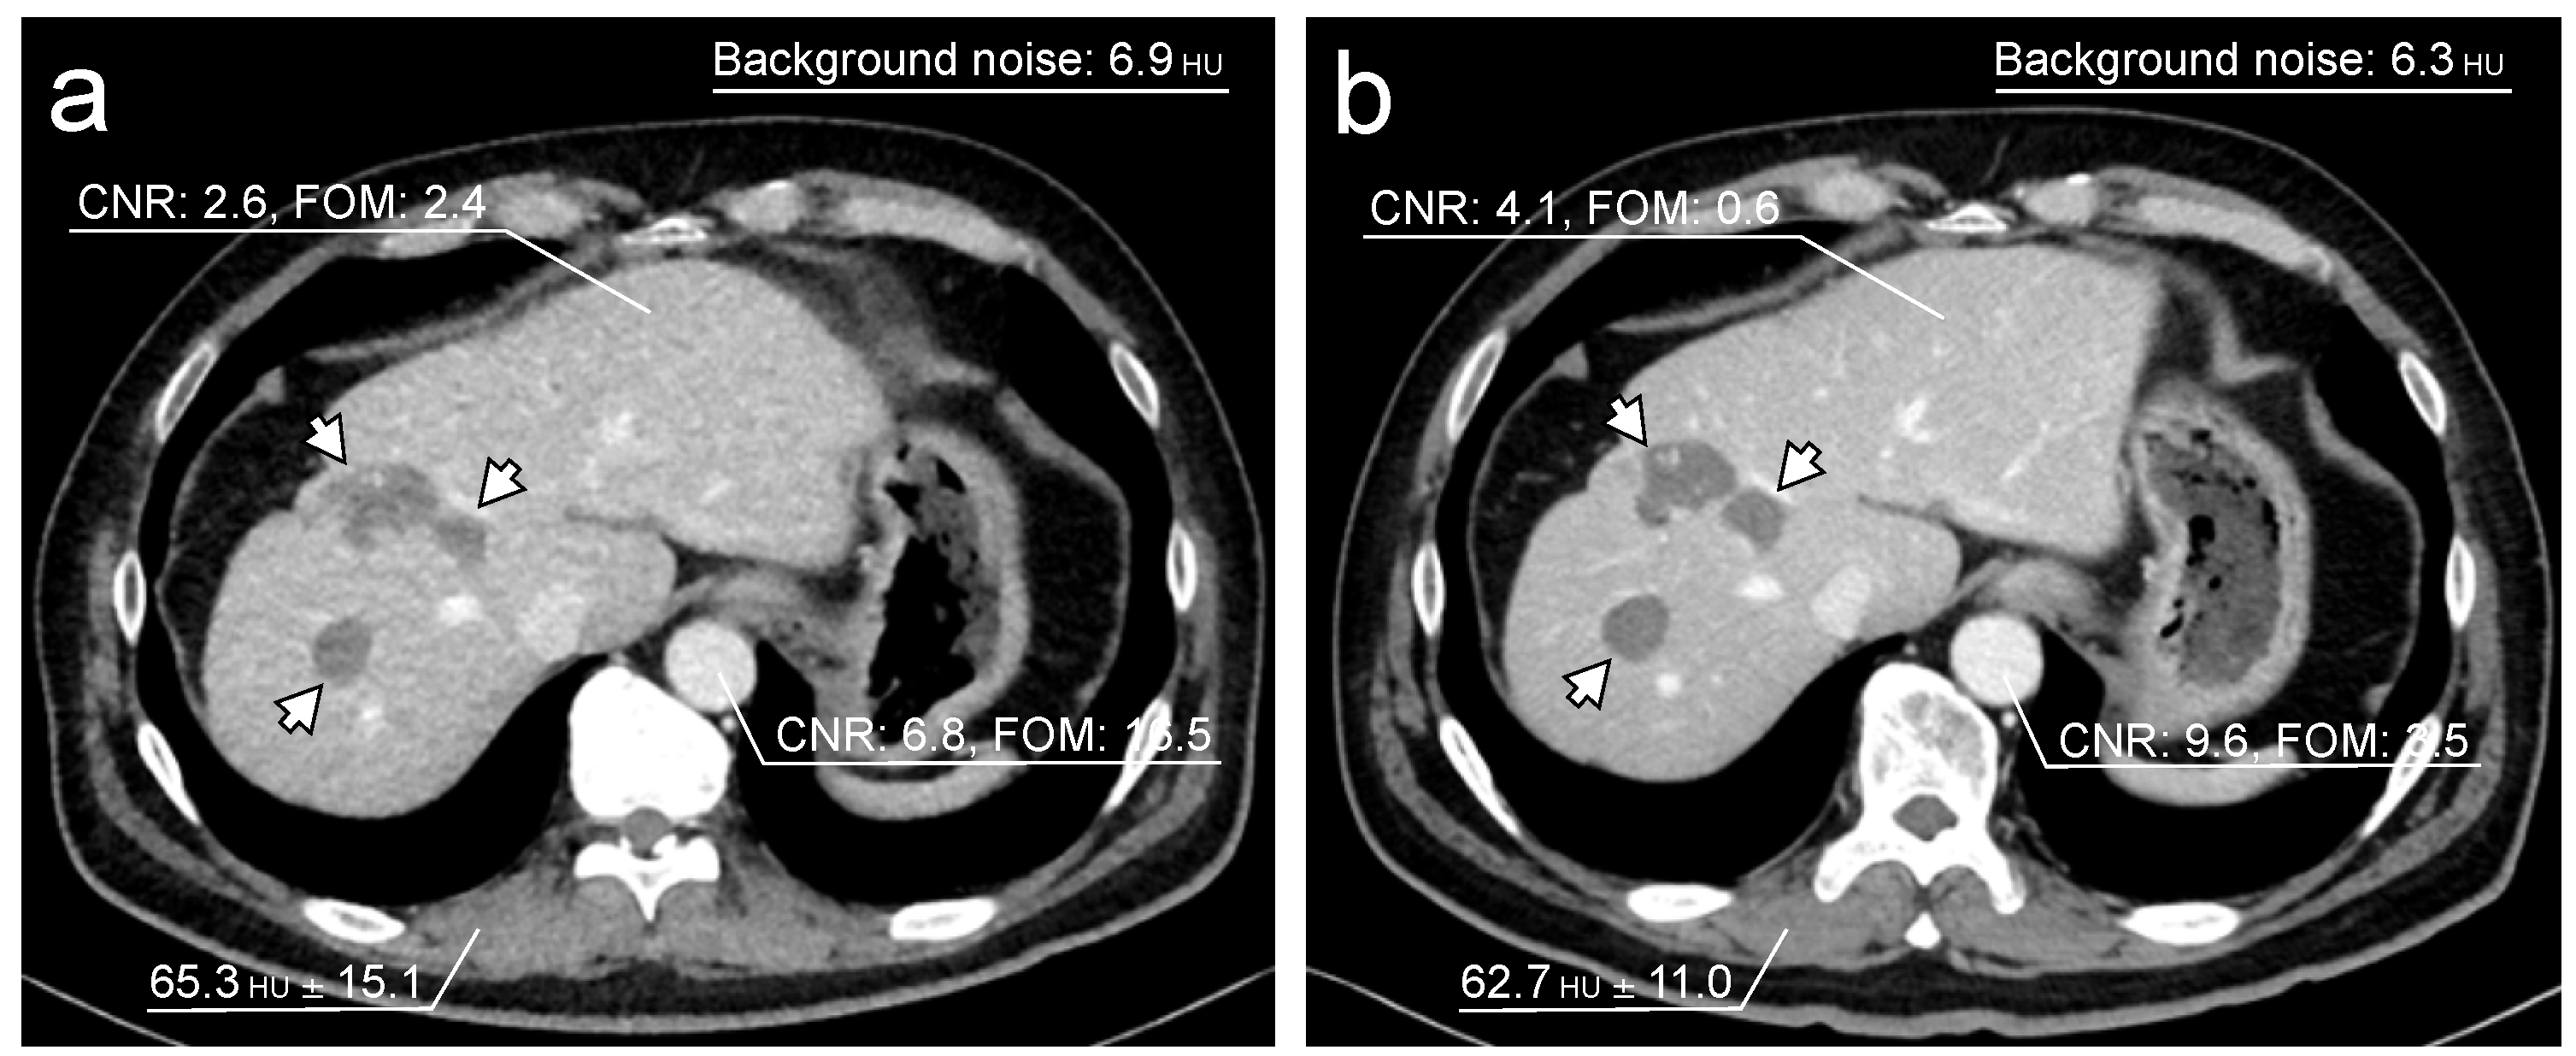

| ST120kV Protocol | TF100kV Protocol | p Value | |

|---|---|---|---|

| CNR of liver | 2.76 (1.38–4.03) | 2.13 (1.42–2.73) | <0.0001 |

| CNR of abdominal aorta | 5.81 (4.76–7.52) | 4.08 (3.39–5.02) | <0.0001 |

| FOM of liver (mSv−1) | 0.36 (0.09–0.93) | 2.24 (0.89–4.07) | <0.0001 |

| FOM of abdominal aorta (mSv−1) | 1.81 (1.19–3.16) | 8.62 (5.98–14.1) | <0.0001 |

| Background noise | 6.04 (5.45–6.93) | 8.36 (7.61–8.86) | <0.0001 |